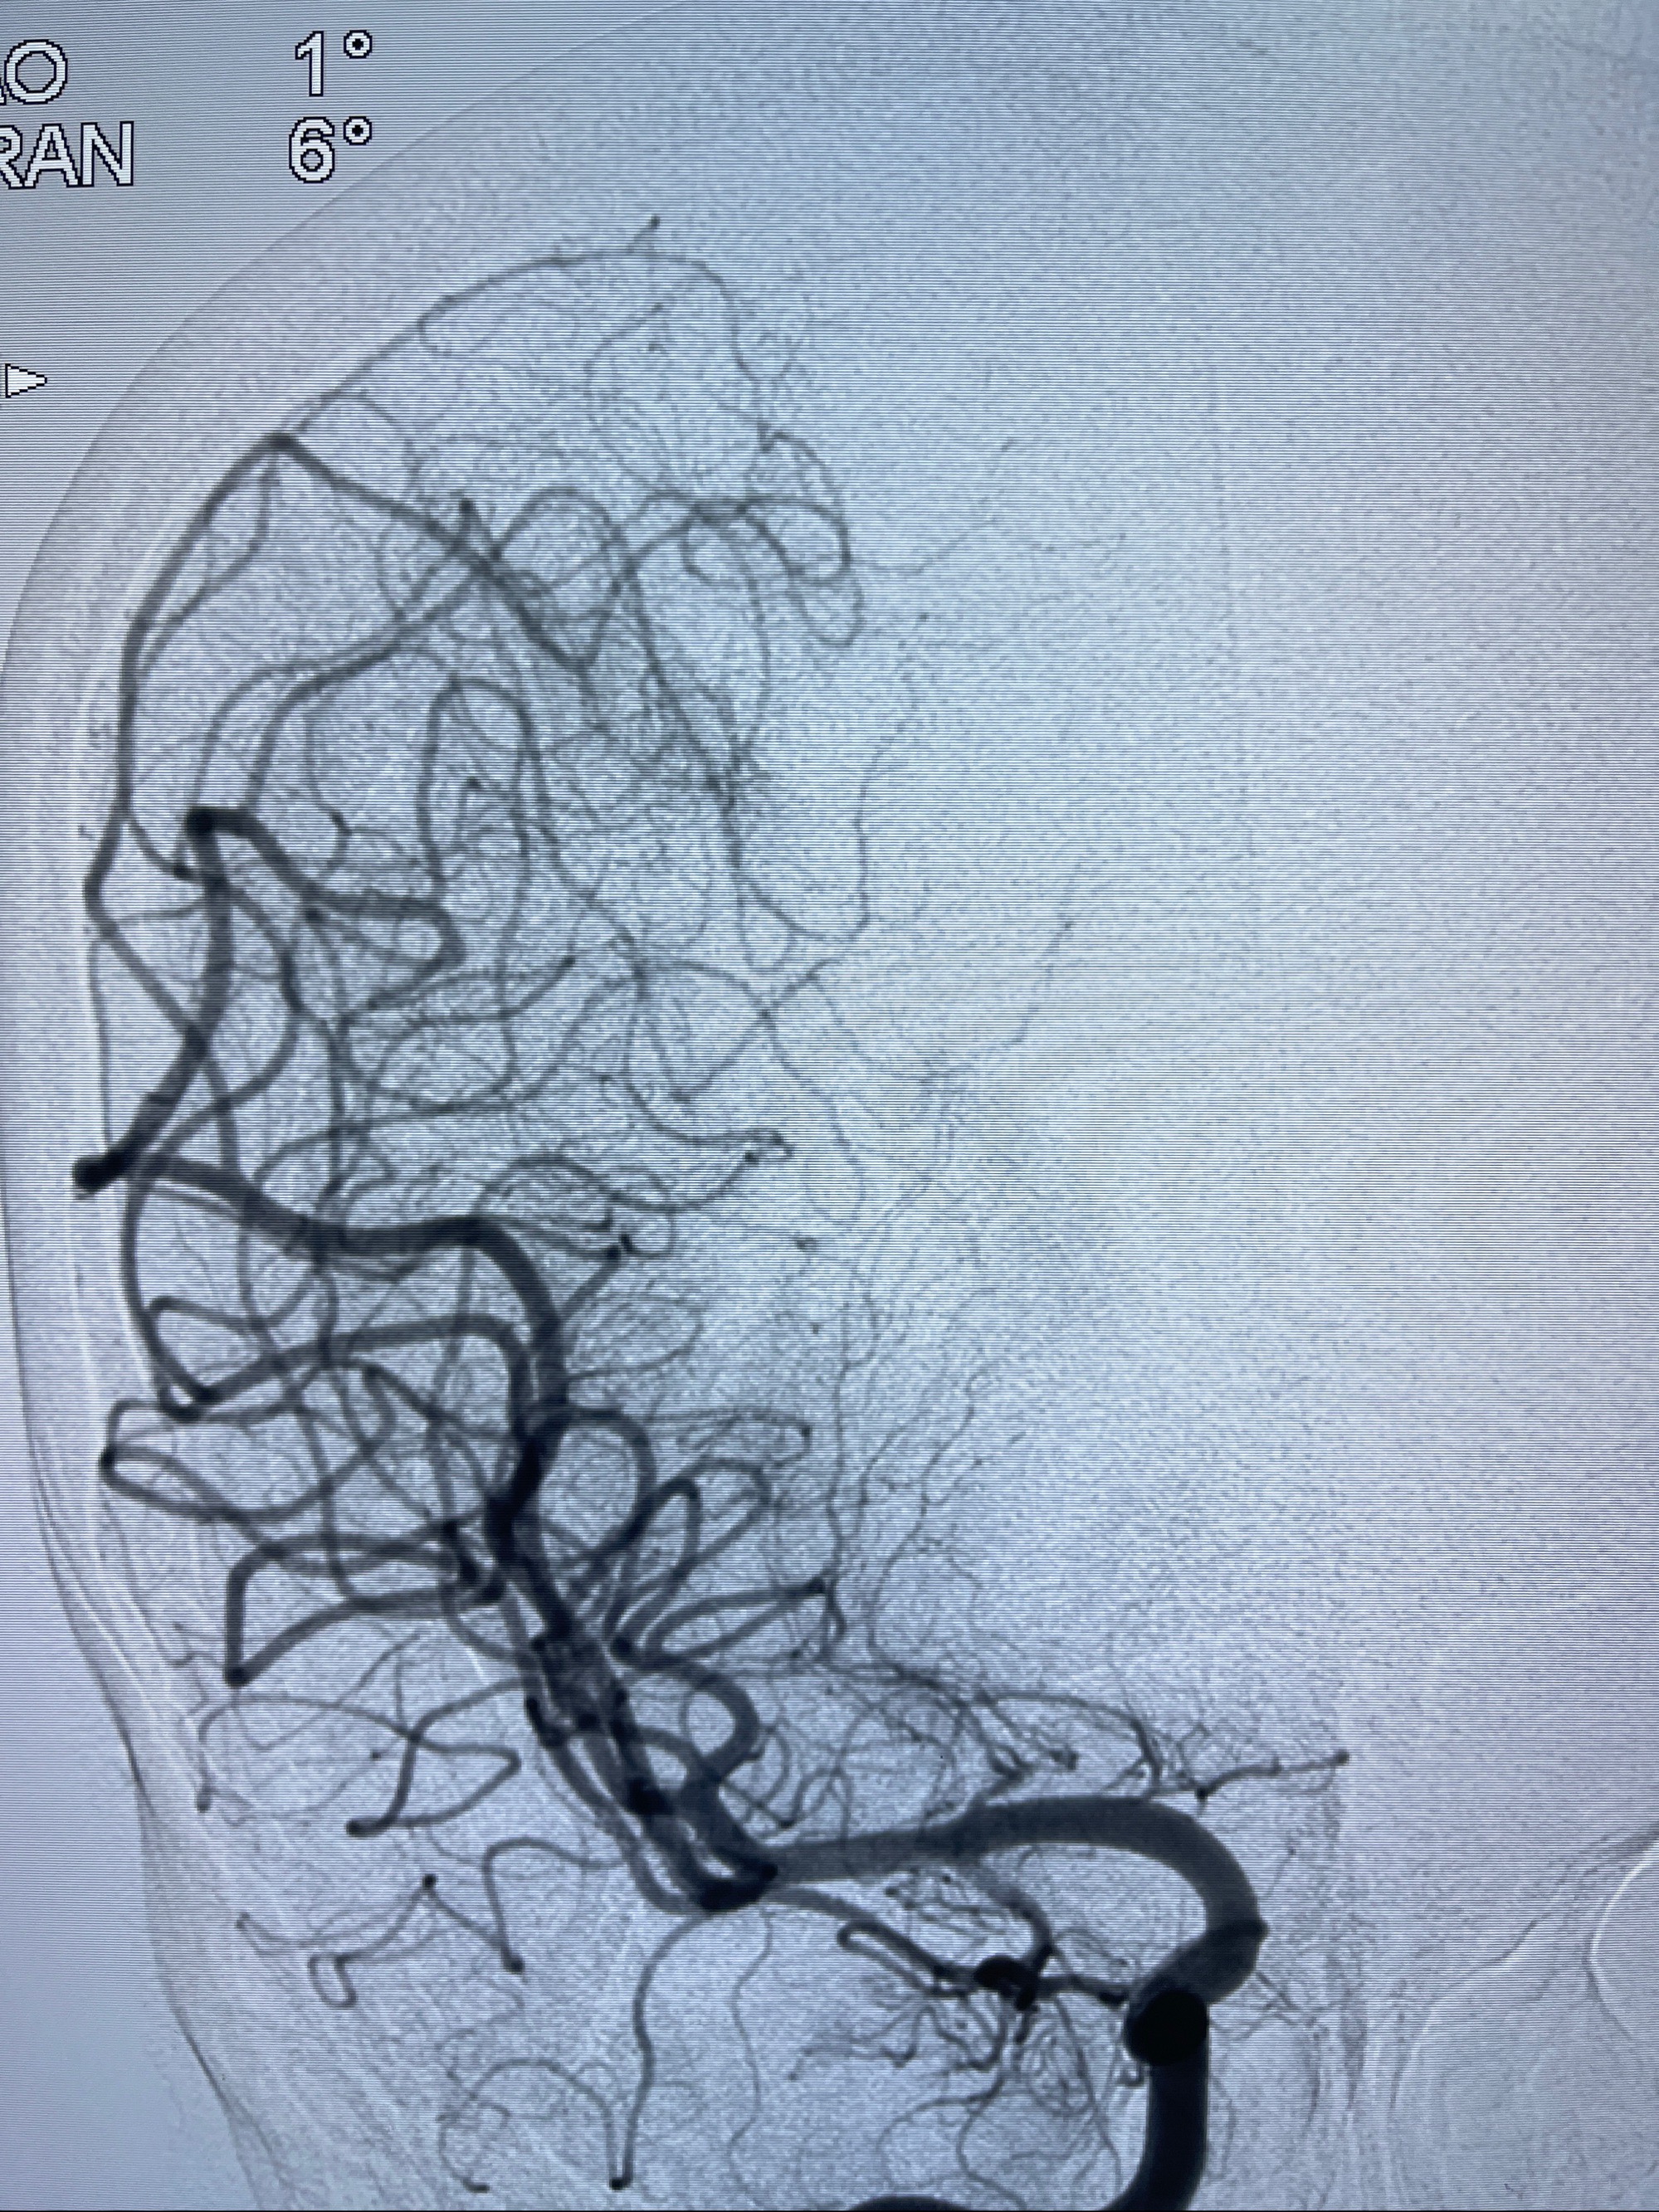

2023-08-14DSA:

左侧大脑中动脉动脉瘤,约2.6-2.8-3.4-2mm大小(瘤颈部、瘤体部、瘤高)